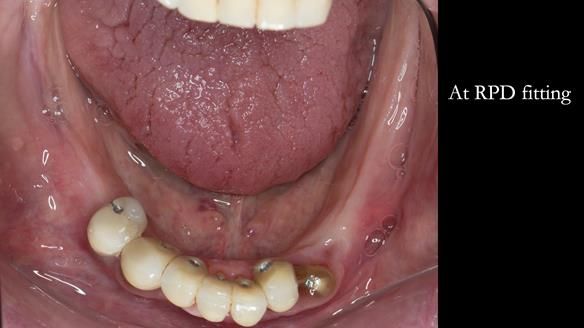

We began with the lower jaw.

A posterior implant 47 had lost integration and was infected. This was removed.

Ken did not want further implant surgery.

Instead, we made a Scandinavian-style, metal-based lower RPD.

It was made promptly, then relined gradually over the following year

to optimise fit, comfort, and support.